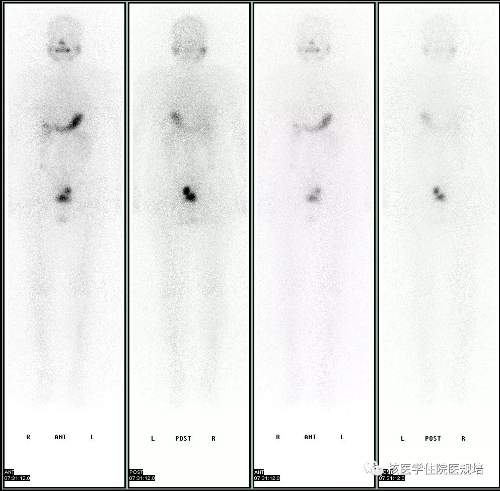

图1.131I全身前后位平面显像

口服131I5.55 GBq后3天行全身显像(图1),结果见:颈部甲状腺区域未见明显异常示踪剂浓集区;口鼻部及胃肠道可见生理性示踪剂摄取;盆腔内膀胱左上方可见一团片状不规则异常示踪剂浓集区,进一步行相应区域SPECT/CT后,见该浓聚灶位于乙状结肠,CT可见一由肠腔向外突出的囊袋影(图2)。全身其他部位未见明显异常显像剂摄取。